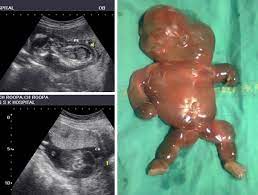

5. Describe the Etiologies of Non-Immune Hydrops. With Dr. Aditya Nimbkar

Dr. Aditya Nimbkar breaks down the definition, etiologies, antenatal evaluation, and postnatal workup of Non-Immune Hydrops Fetalis in a way you’ll never forget.

One of the most frequently asked topics in the DNB OBG exam — now made crystal clear.

• System-wise causes: Cardiovascular, Chromosomal, Thoracic, Infectious

• Parvovirus B19, alpha-thalassemia, Turner syndrome & more

• Antenatal red flags and neonatal assessment